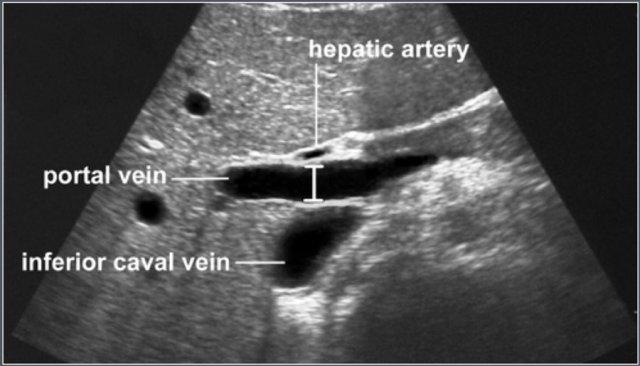

Tĩnh mạch cửa

Vật liệu và Phương pháp

Nghiên cứu được thực hiện trên 150 trẻ em trong độ tuổi từ 0–16 tuổi, không có bằng chứng lâm sàng về bệnh lý gan hoặc đường ruột, được thực hiện siêu âm ổ bụng.

Tĩnh mạch cửa được khảo sát trên mặt phẳng dọc từ chỗ hợp lưu lách-mạc treo tràng đến rốn gan.

Đường kính trước-sau tối đa được đo tại vị trí động mạch gan bắt chéo qua tĩnh mạch cửa.